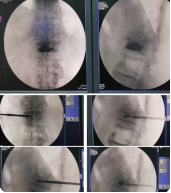

脊柱内镜及微创诊疗技术